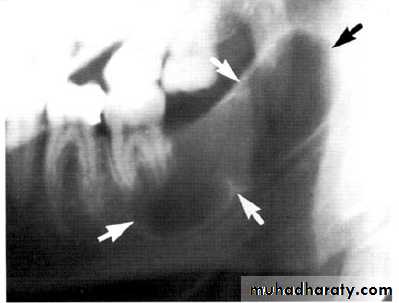

Multilocular appearance, expansion (arrowed) and considerable displacement of the adjacent teeth.

Buccal and lingual expansion (arrowed) and the undulating cortical border.

Large multilocular aneurysmal bone cyst

in the ramus with marked expansion andthe displacement of/8.

It is non-neoplastic ,exaggerated , localized, proliferative lesion of vascular tissue, containing giant cells.

It’s a variation of the central giant cell granuloma , can be diagnosed only by histological examination